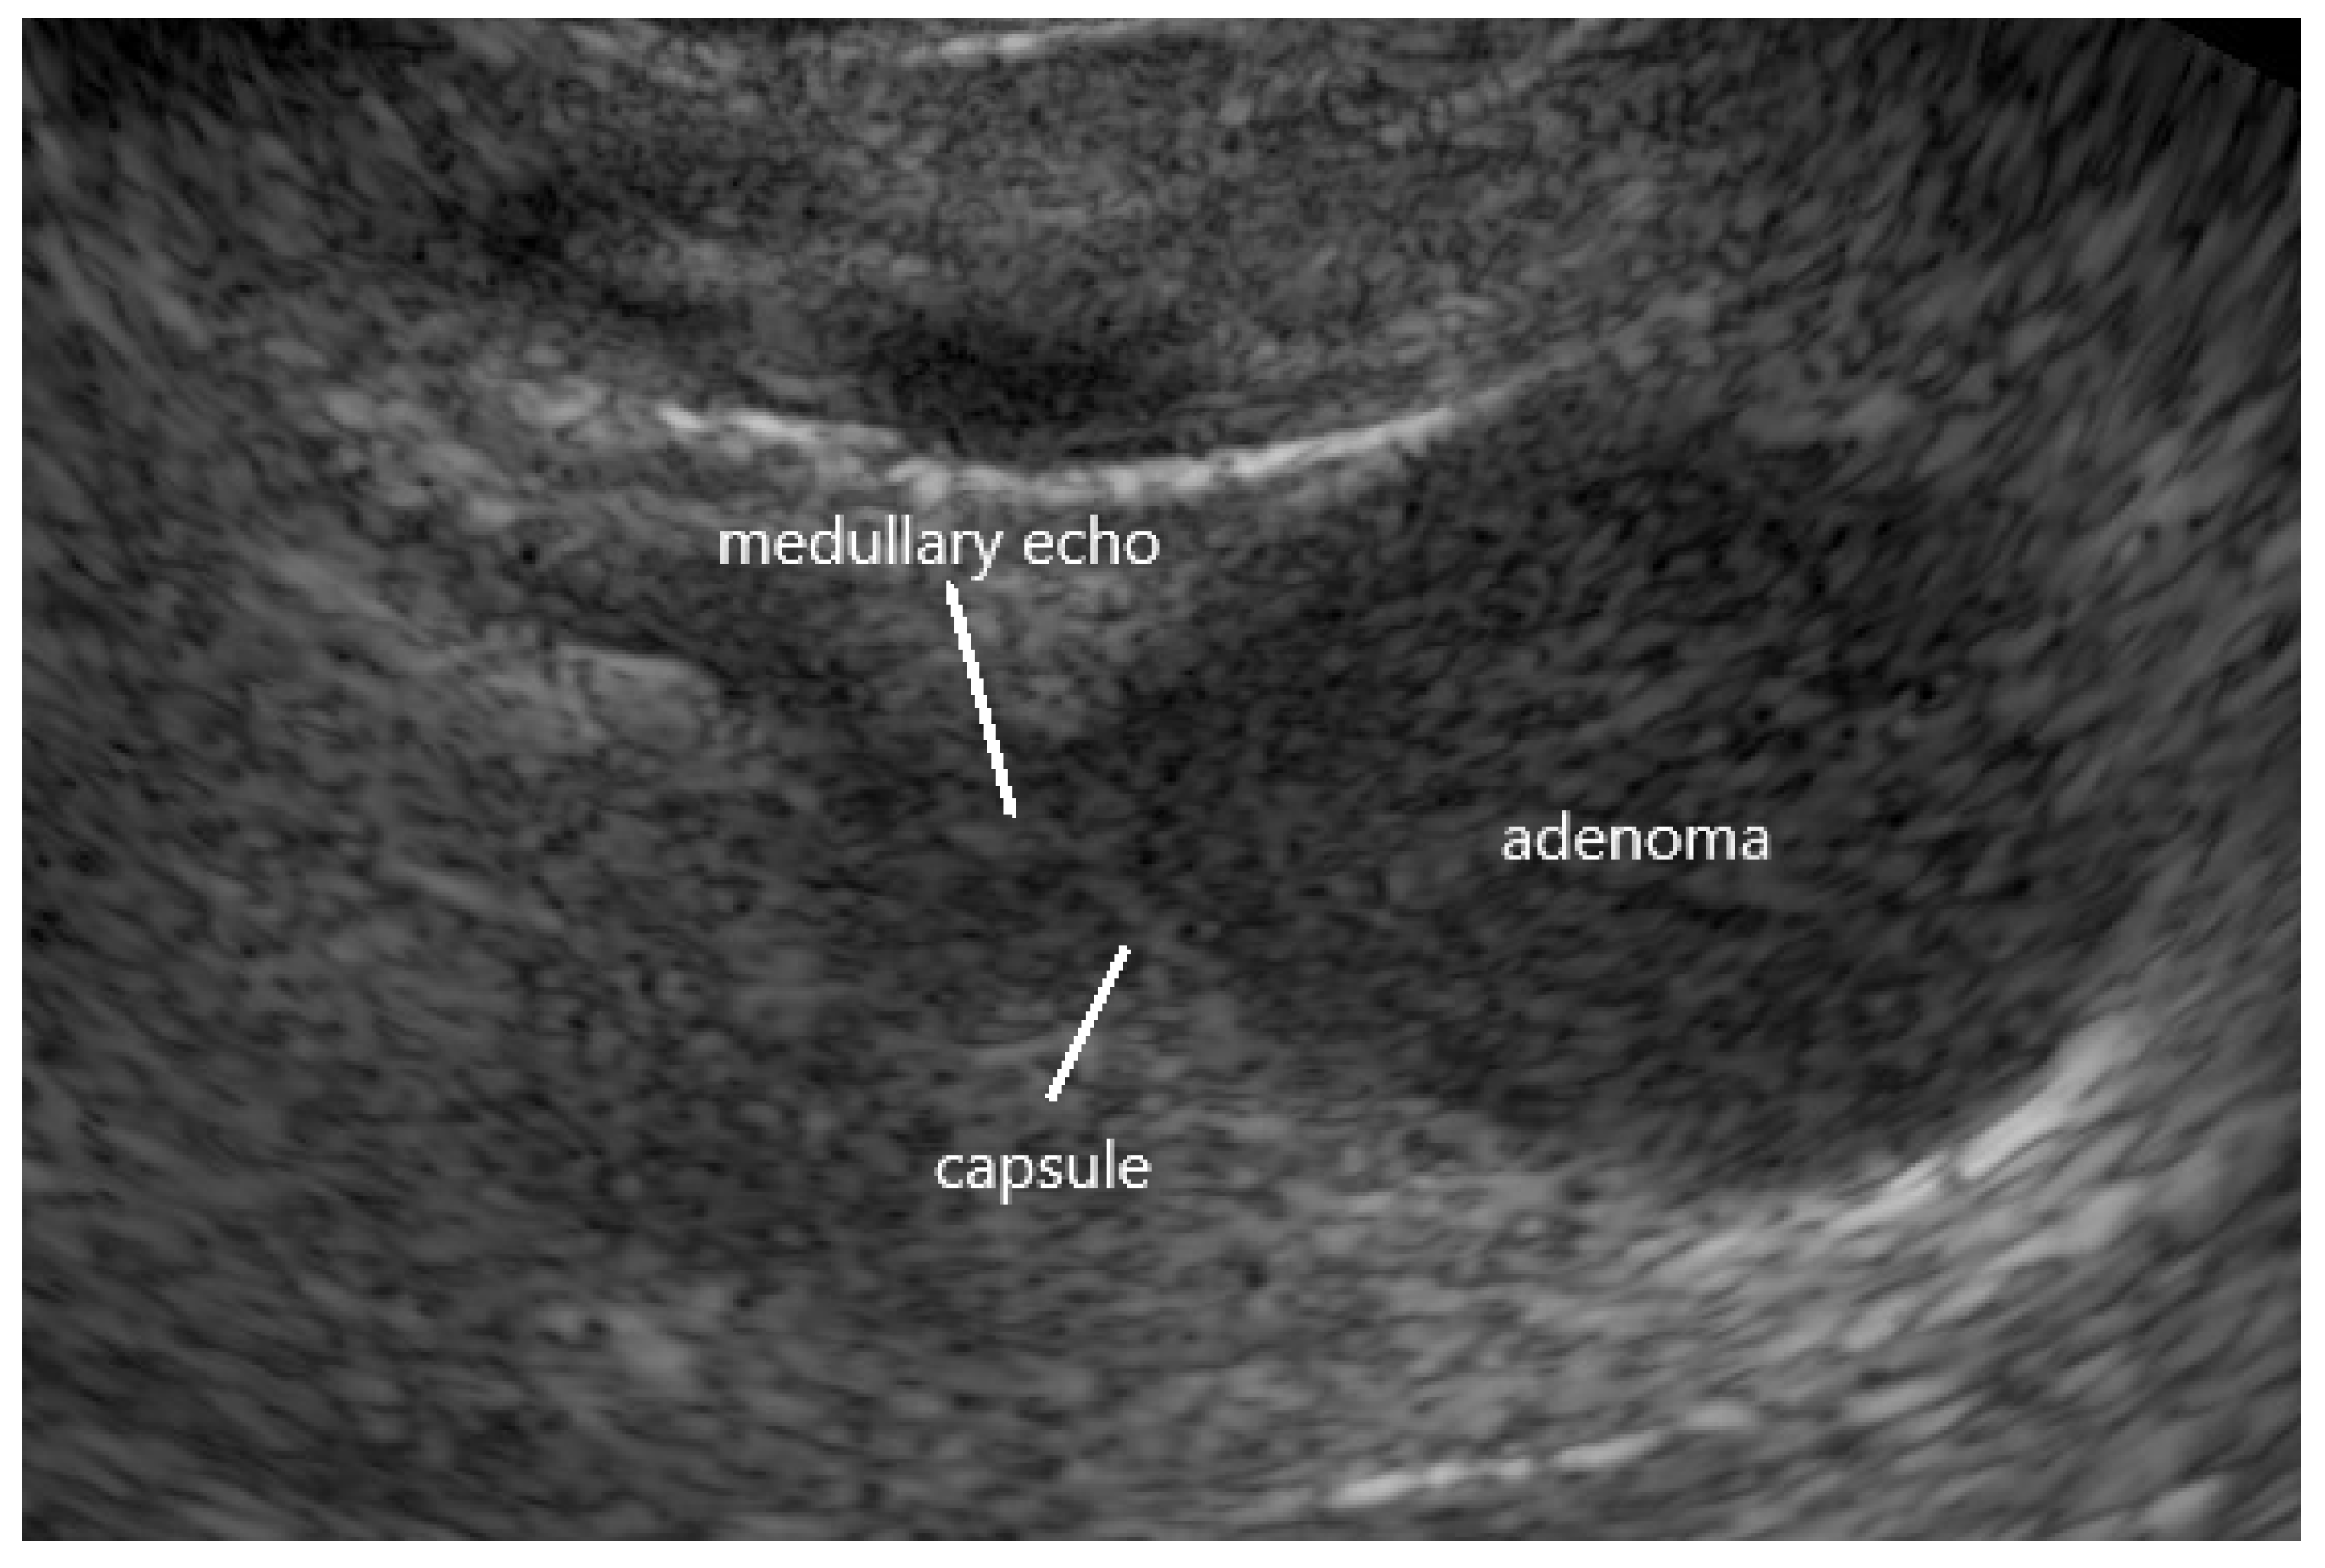

| Primary Aldosteronism (Conn’s Adenoma) | Identification of an adrenal lesion with typical morphological features of an aldosteronoma. Defining the remaining parts of the ipsilateral and the contralateral adrenal as morphologically inconspicuous/normal. Planning of surgical intervention: selective adenomectomy possible? |

| hypoechoic echogenicity | 82% |

| largely homogenous echostructure | 72% |

| hyperechoic capsular tumor margin | 93% |

| termination of medullary echo at tumor margin | 97% |

| diameter ≤ 2 cm | 77% |

| no/only discrete hyperperfusion (duplex) | 94% |

| tumors fulfilling at least four criteria | 98% |

| tumors fulfilling at least five criteria | 91% |